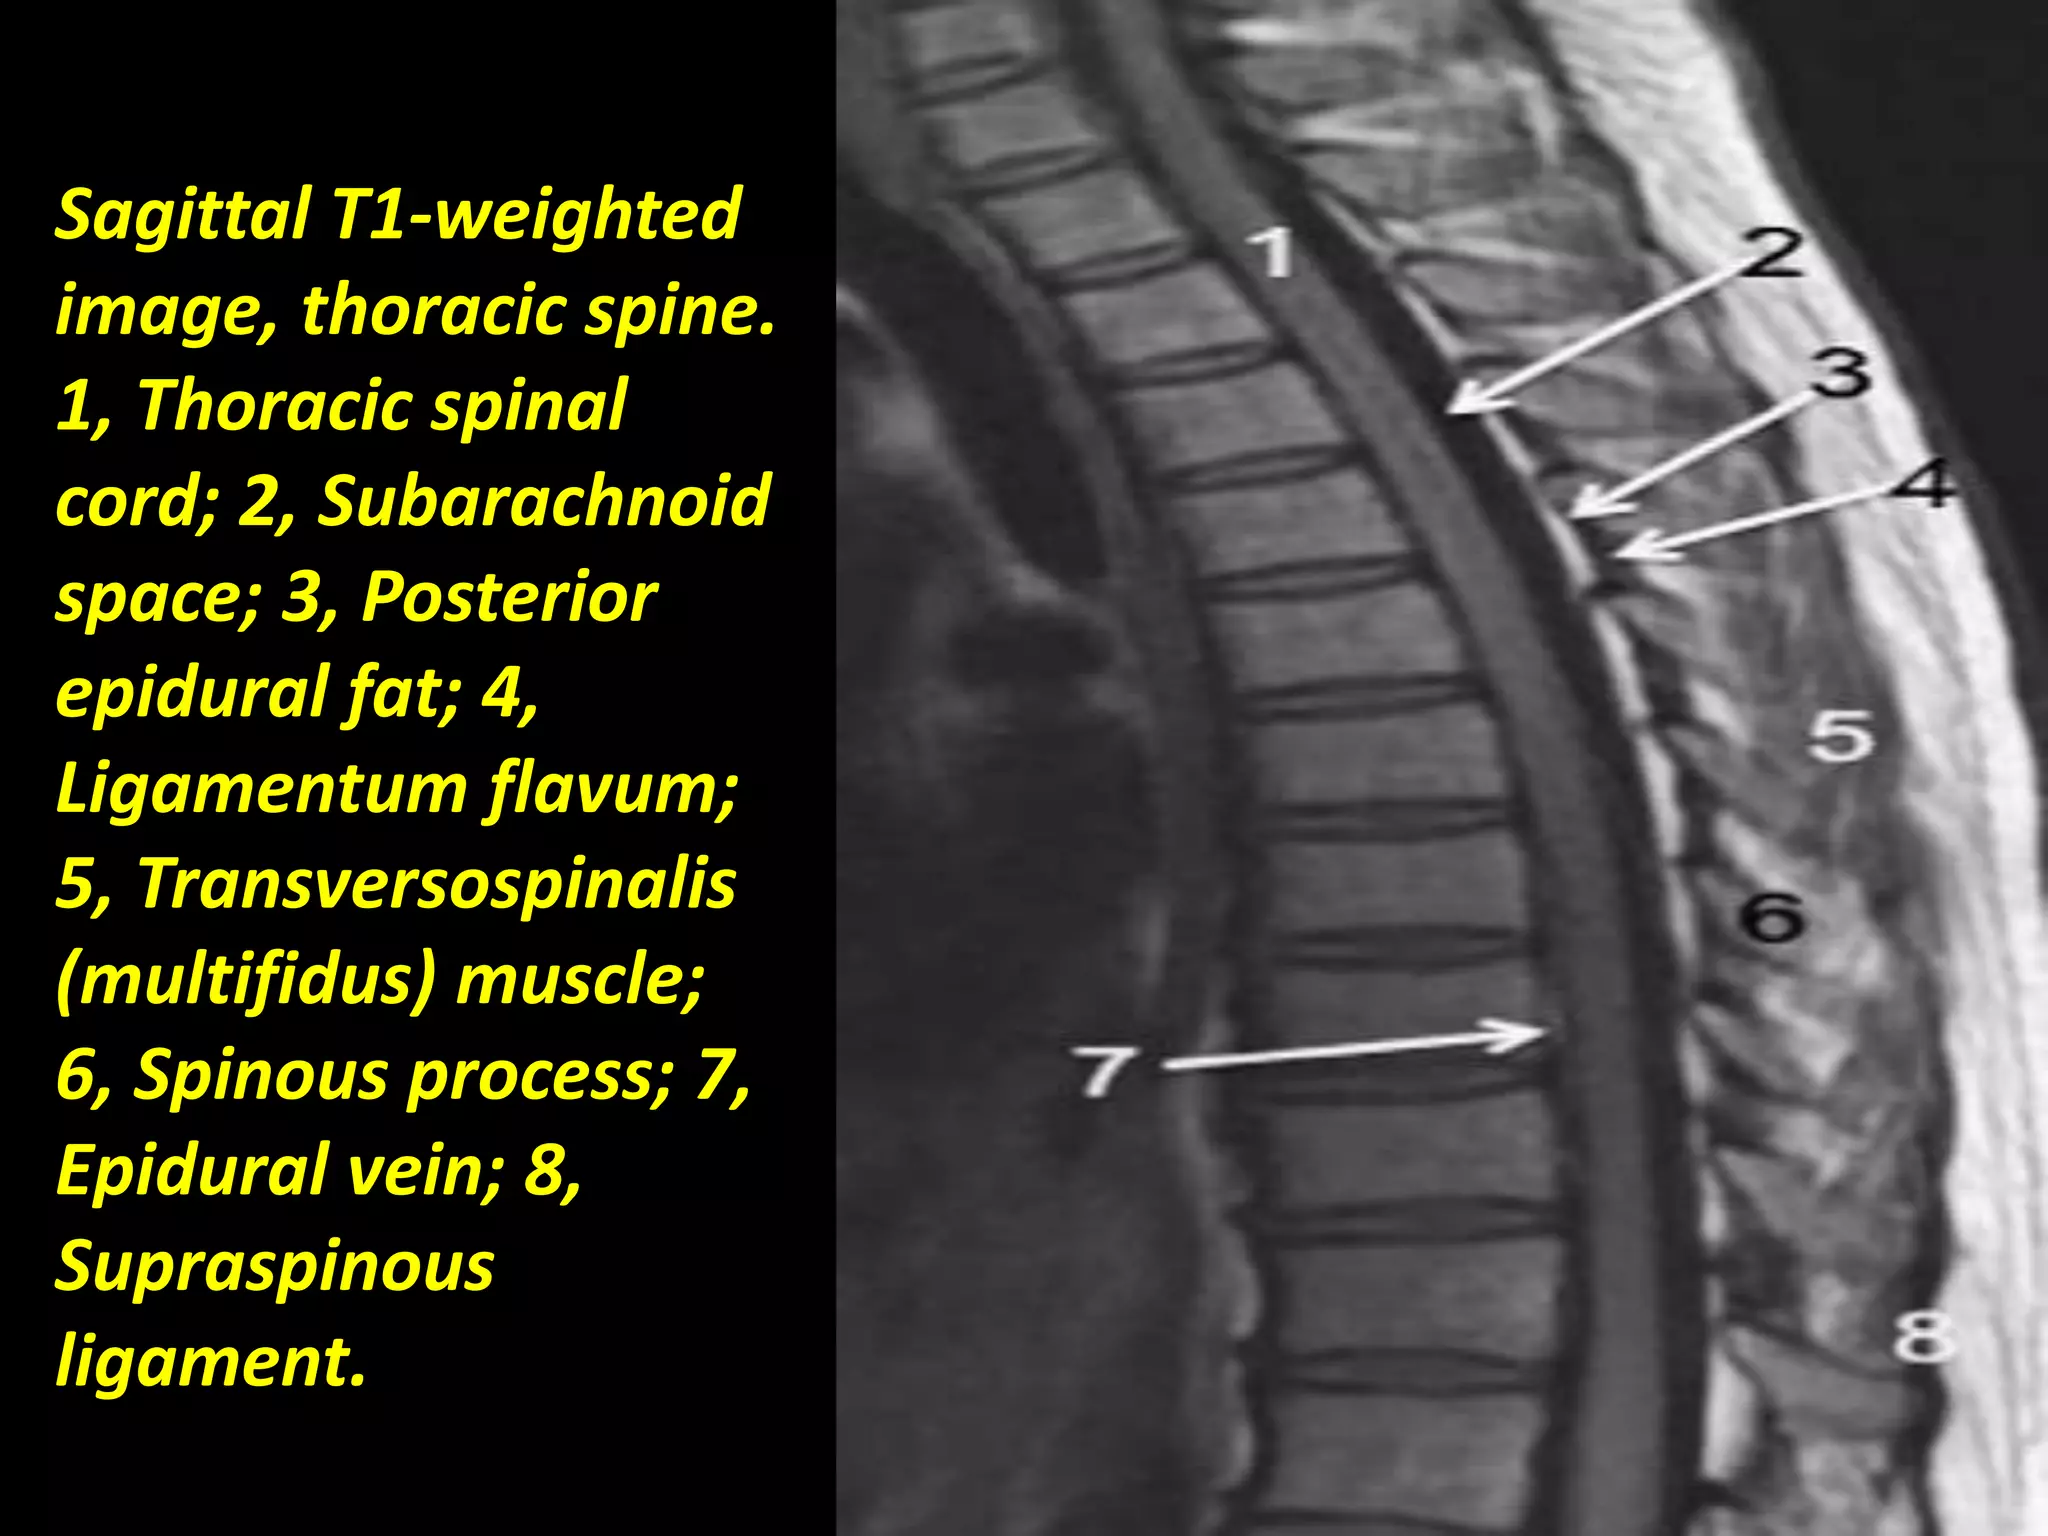

Sagittal T1-weighted

image, thoracic spine.

1, Thoracic spinal

cord; 2, Subarachnoid

space; 3, Posterior

epidural fat; 4,

Ligamentum flavum;

5, Transversospinalis

(multifidus) muscle;

6, Spinous process; 7,

Epidural vein; 8,

Supraspinous

ligament..

Sagittal T1-weighted image,thoracic spine. 1, Thoracic spinal cord; 2, Subarachnoid space; 3, Posterior epidural fat; 4, Ligamentum flavum; 5, Transversospinalis (multifidus) muscle; 6, Spinous process; 7, Epidural vein; 8, Supraspinous ligament..